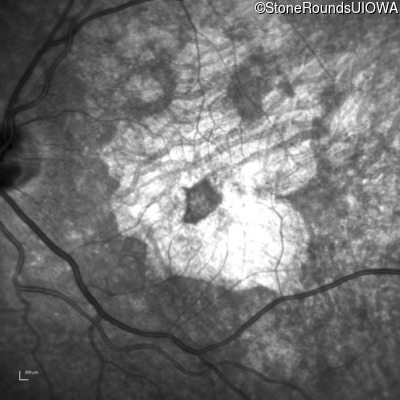

Infrared Fundus Photograph - Right - 20/32 +2

Exemplar